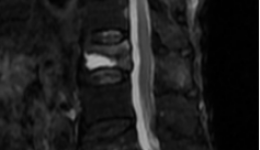

微创之光|茂医脊柱外科:以微小切口解决患者腰椎间盘突出大问题

“手术效果真好!今早起来发现腰腿不痛了,请问今天我可以起床活动了吗?”术后第二天早上查房时,34岁的杨先生激动地询问茂名市人民医院脊柱外科一区主任医师梁晓,兴奋之情溢于言表。据了解,杨先生被严重的腰椎间盘突出症困扰折磨了一年多,右腿...